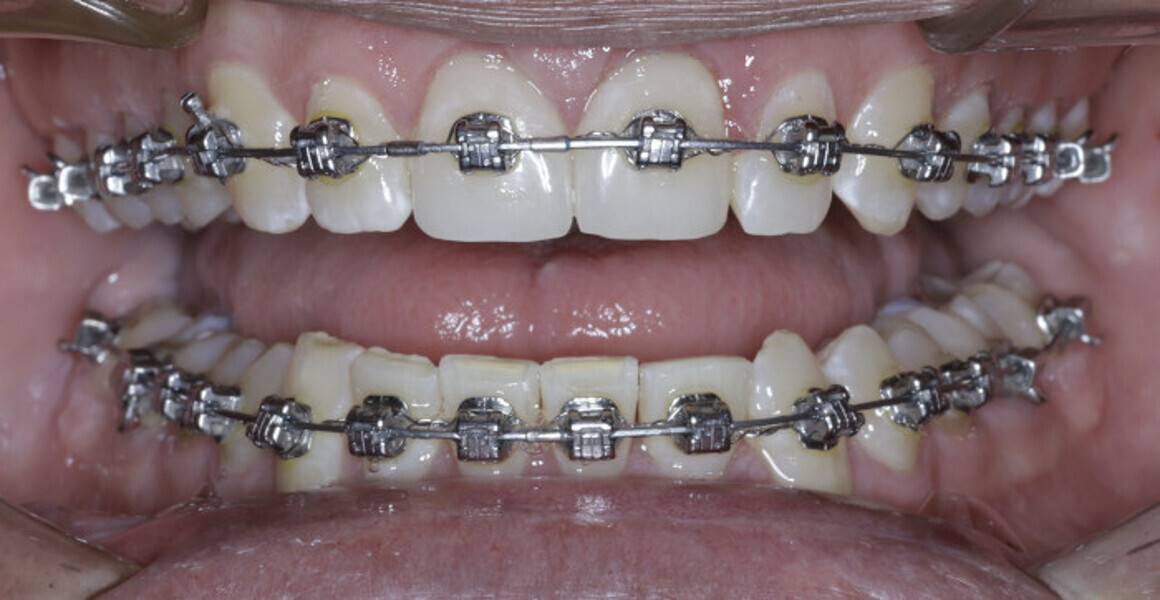

New Age orthodontics and orthopaedics with temporary anchorage devices